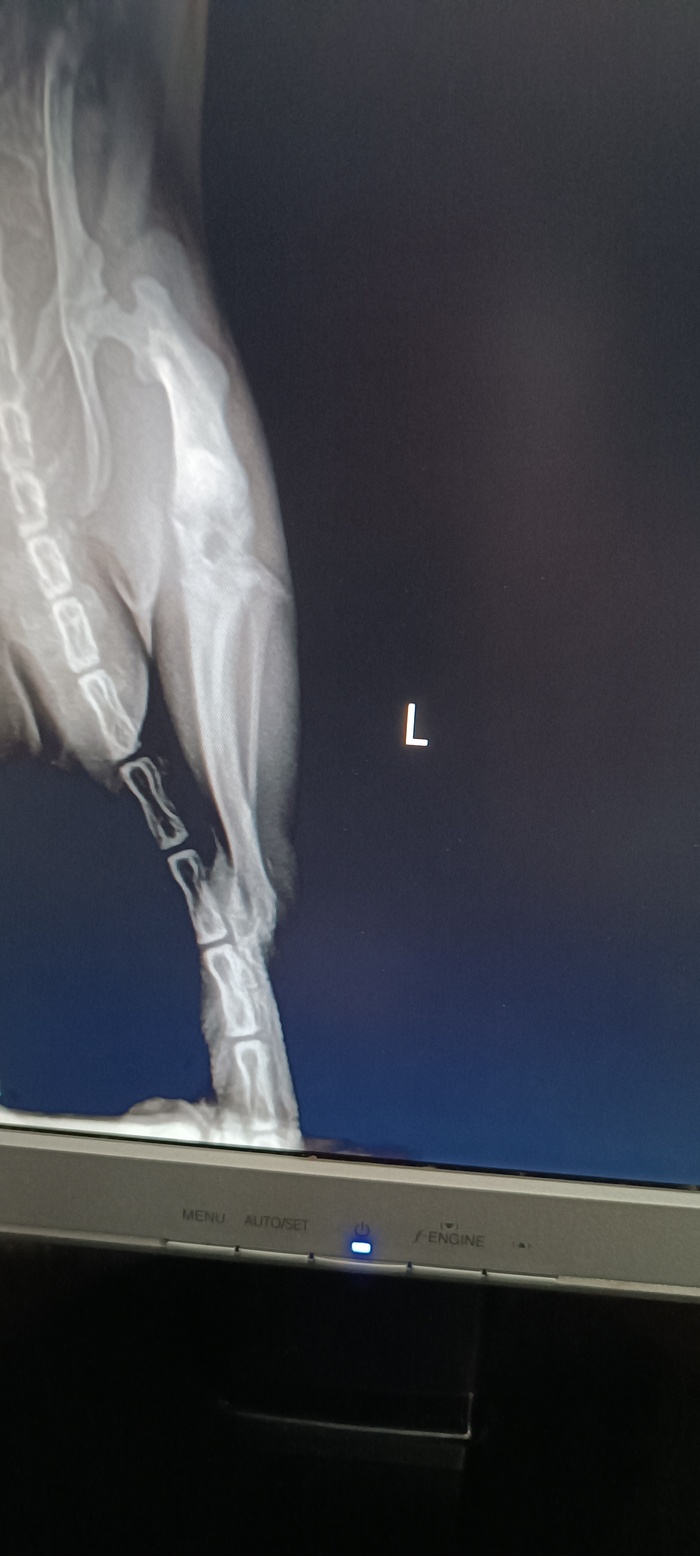

Проблемы с лапой

У Сталина опухла левая задняя лапа. В ночь с 21 на 22 июня. На нее наступать не мог. 23 июня пошли к ратологу. Сделали рентген. Диагноз: повреждение сустава. Отек из-за удара лапы. Сказали ограничить подвижность, прописали вемелкам 0,5мг, давать по 1/3 таблетки дважды в день. Ограничить движение.

Рентген